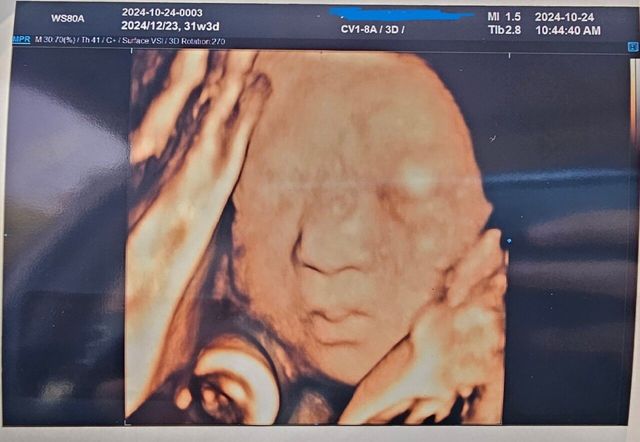

시험관 시도 2번만에 딸아이 가졌습니다.

예정일이 12월 23일인데... 24일이나 25일날 태어나주면 크리스마스랑 생일이랑 퉁치면 좋을거 같은데 말이죠ㅎㅎㅎ

(입쪽이 저닮은거 같은데;;; 아놔 큰일인데 딸인데... 튼튼아 나닮으면 안돼~~~)